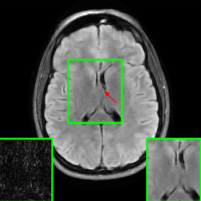

Figure 10 presents visual comparison of image reconstructions and their associated reconstruction errors within a closely examined region. Each image in the figure includes two inset panels in the bottom-left and bottom-right corners. The bottom-left inset panel, enclosed within a green bounding box, serves as a reference for the region of interest in the image. In contrast, the bottom-right inset panel depicts an error map in relation to the ground truth. Notably, our method stands out in its ability to capture more features from the original image, surpassing the performance of alternative methods (as also evident from the reported PSNR values).

In Figure 12, we replicate the experiment conducted in Figure 6, this time utilizing the brain dataset. Notably, MoDL underwent fine-tuning using perturbed purified examples sourced from the training set of the brain dataset. When comparing the results of our proposed method with other approaches, we find that the observations of Figure 6 remain consistent. For the PGD case (third column), our method reports an average SSIM of nearly 0.91 whereas Vanilla MoDL (the DL-reconstructor considered in this experiment) reports an average SSIM of approximately 0.775. An important point to highlight is that the pre-trained DM employed in our purification stage for this experiment was originally trained exclusively on knee data, without any exposure to brain data. This underscores the robust generalization capabilities of the diffusion purification process within our approach, extending its effectiveness to previously unseen MRI datasets.